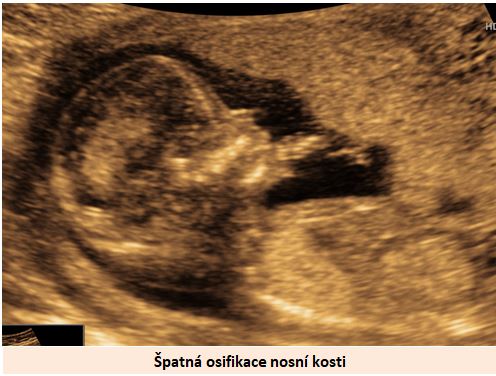

Ultrazvuková diagnostika se při screeningu v 1. trimestru opírá o šířku podkoží v záhlaví plodu, osifikaci nosní kůstky a nálezu abnormálních průtoků v srdci plodu (trikuspidální regurgitace, reversní tok v ductus venosus).

Pracoviště se zkušenostmi v prenatální diagnostice a s dobrým přístrojovým vybavením je schopno vyslovit podezření na tento syndrom ve více jak 90% případů již při ultrazvukovém vyšetření ve 12-13. týdnu těhotenství. .